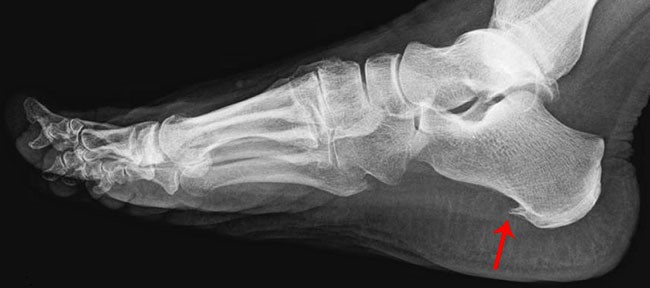

Внешне пяточная шпора (фото) не видна. Чтобы ее точно диагностировать, обязательно нужен рентген.

Вот фото пяточной шпоры на рентгеновском снимке.

Обычно костный вырост обнаруживают в том месте, где сухожилия прикреплены к пяточной кости. Размер пяточной шпоры всего от 3 до 12 мм, но, тем не менее, при надавливании на нее значительным весом возникает боль, которую трудно терпеть. Сам вырост не имеет нервных окончаний, а это значит, что болеть он не может. Но он воздействует на ткани ступни, а это как раз и есть причина боли и дискомфорта. Боль бывает настолько сильна, что больному приходится при ходьбе опираться на носок, так как полностью стать на ступню, пораженную пяточной шпорой, даже самой крошечной, невозможно. Если болезнь пустить на самотек, то больной постепенно начнет прихрамывать. А при продолжительном протекании заболевания развивается боковое плоскостопие. Шпора образуется на одной из ступней или на двух сразу. И это действительно проблема. На носках далеко не уйдешь, даже с помощью трости. Такое положение вещей способно изменить даже образ жизни: больному придется существенно ограничить передвижения, отказаться от ношения тяжестей. К счастью, природа пяточной шпоры исключительно доброкачественная. Тем не менее, болезнь нужно лечить и ни в коем случае не запускать, и раз уж образовалась шпора на пятке, лечение неизбежно.